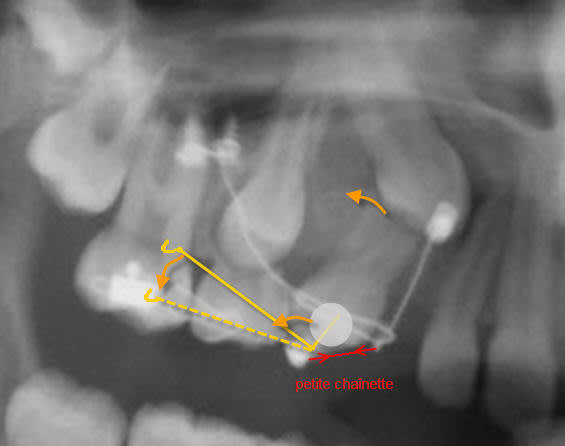

Si Dancha a collé un bouton sur la 14, c'est pas juste pour faire joli , alors je propose une chainette très souple entre la 13 et la 14.

Pour utiliser le bouton coll  on1r2s - Eugenol